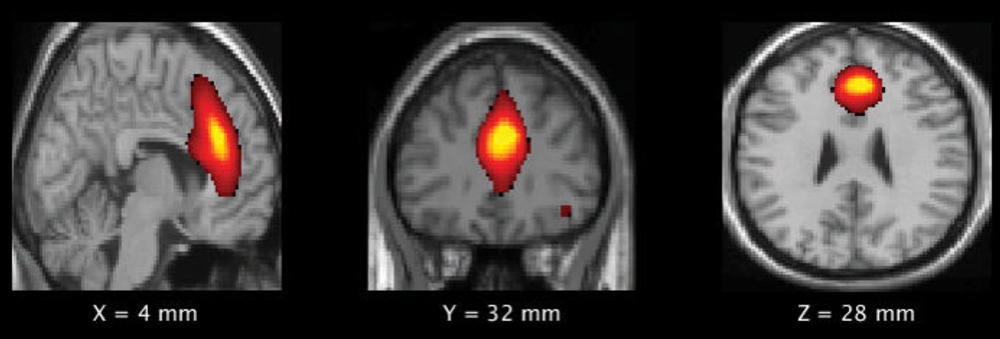

Figure 1. Frontal Default Mode Network (DMN) Component which shows significant difference between the high and low impact players.

The post-season results showed significant increases in power and gray matter volume in the frontal DMN in the high-impact group.

“Disruption in normal pruning has been shown to be related to weaker connections between different parts of the brain,” Murugesan said. “Our study has found a significant decrease in gray matter pruning in the frontal default mode network, which is involved in higher cognitive functions, such as the planning and controlling of social behaviors.”